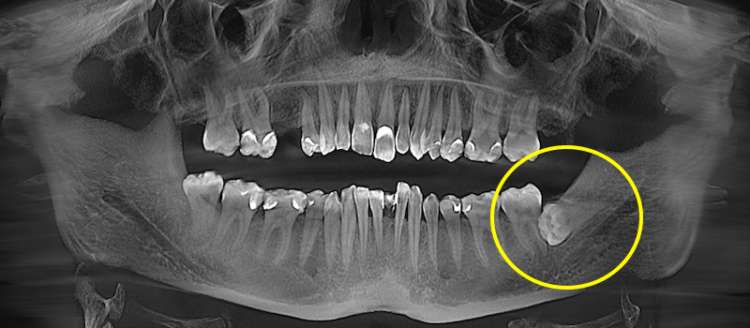

Видалення дистопованого зуба мудрості

Дистопований зуб мудрості — це зуб, який прорізався або частково прорізався, але займає неправильне положення в зубному ряду. Найчастіше він нахилений у бік 7-го зуба, росте під кутом або зміщений у бік щоки чи язика.

Перед видаленням оцінюється його положення на рентгені або КТ: напрямок нахилу, форма коренів, контакт із сусіднім моляром і стан кісткової тканини. Це дозволяє зрозуміти, чи є ризик ураження 7-го зуба та обрати оптимальну техніку видалення.

Під час операції лікар обережно вивільняє зуб із лунки. Якщо зуб має виражений нахил або складну форму коренів, він може розділятися на фрагменти для контрольованого вилучення без надмірного тиску на кістку.

Після видалення лунка очищується від залишків тканин, промивається антисептичним розчином і за потреби закладається гемостатичний матеріал. Відновлення зазвичай супроводжується помірним набряком або дискомфортом у перші дні.